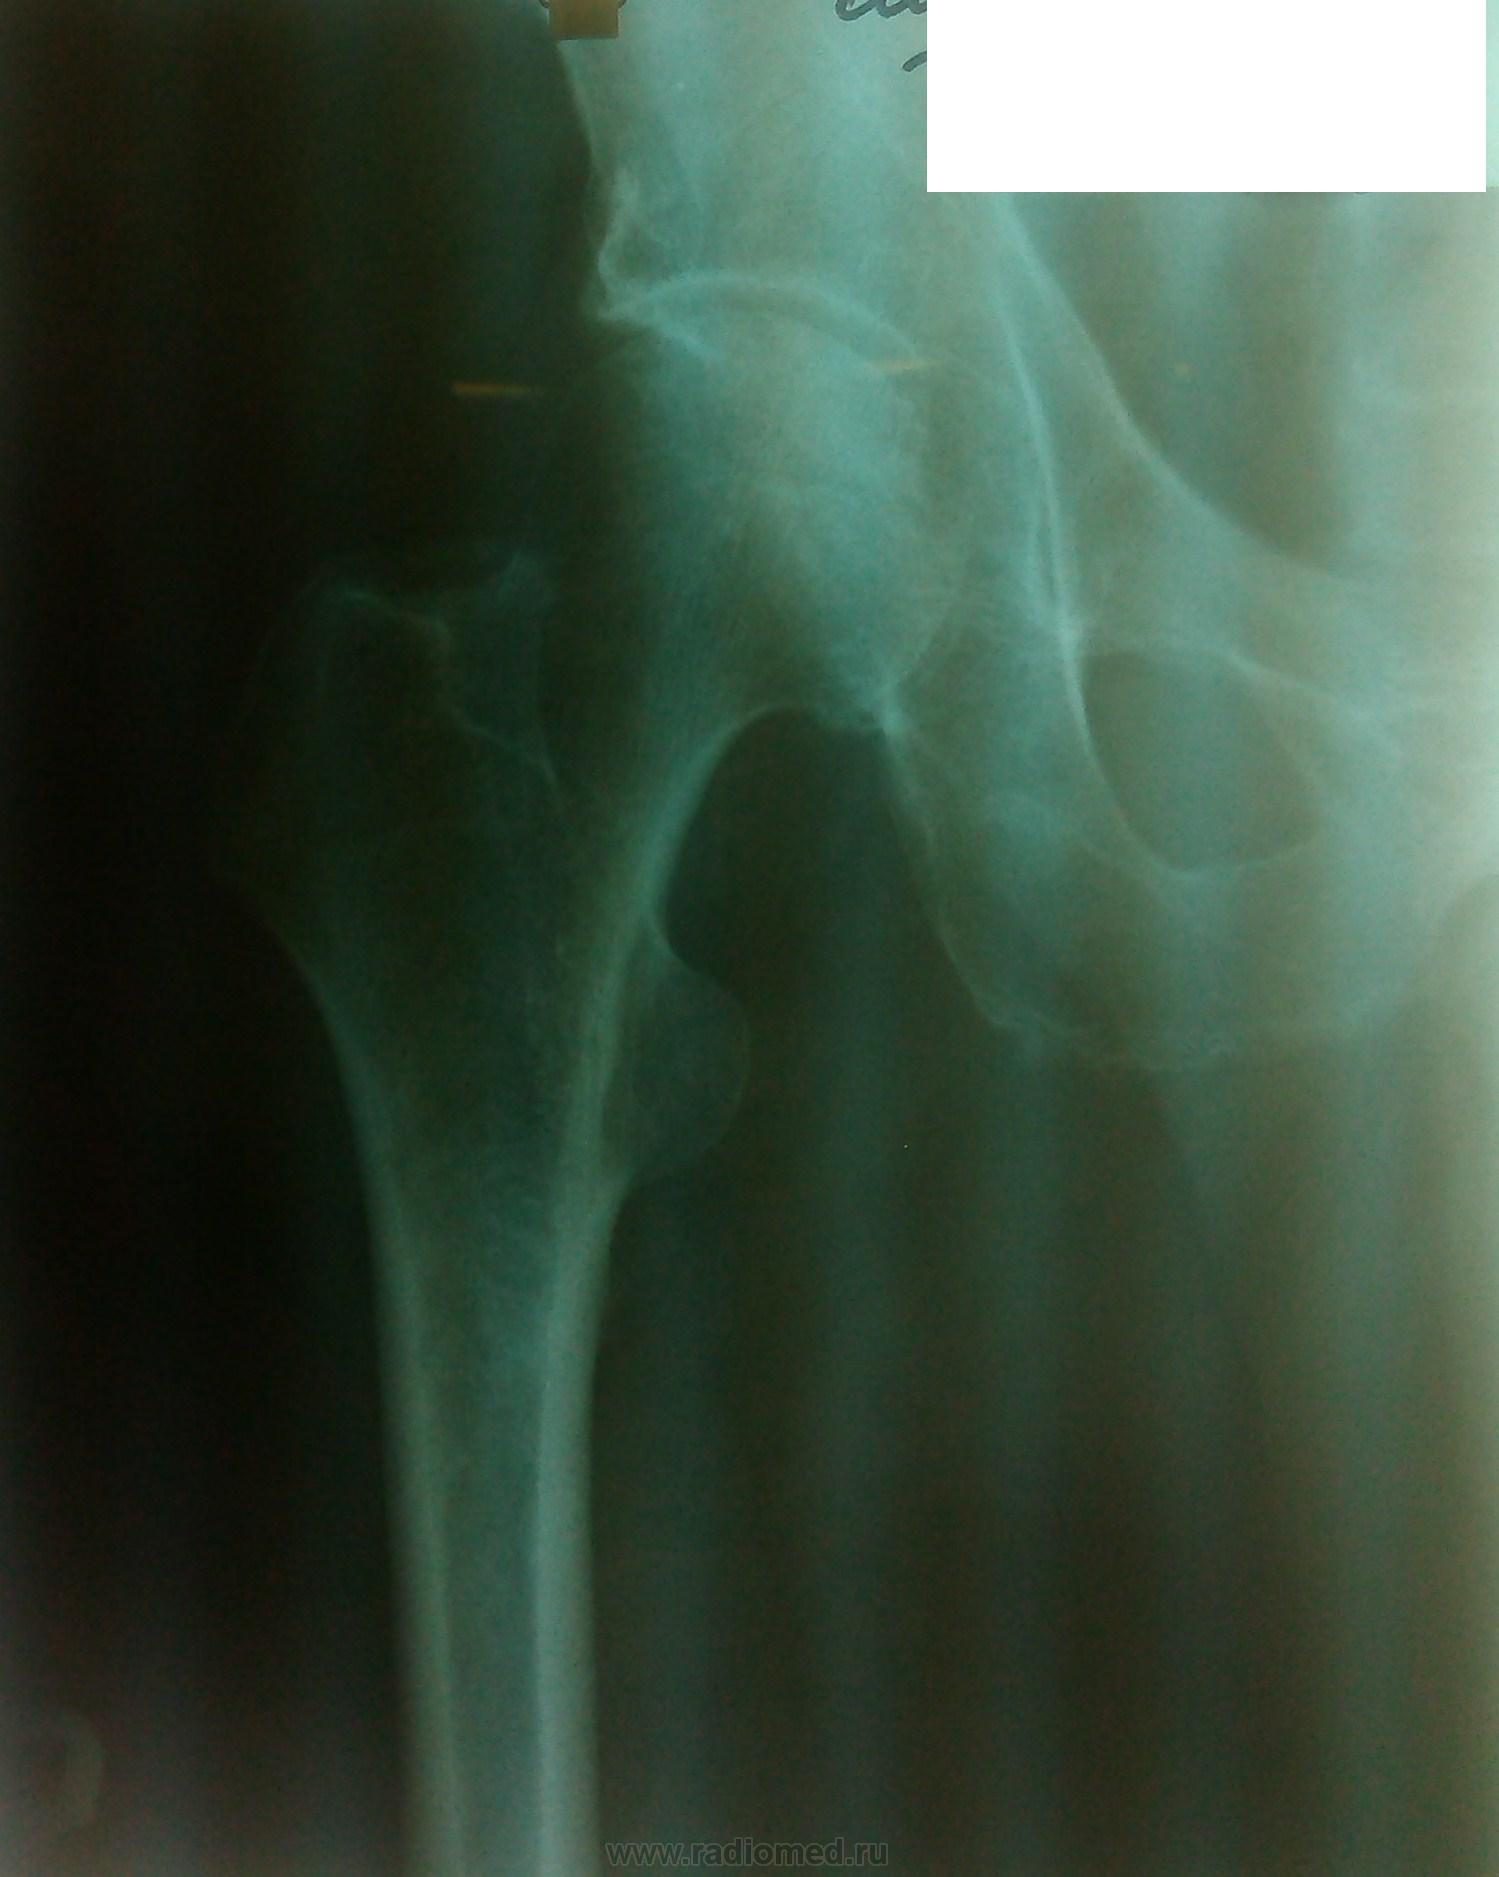

Пол пациента: Мужской пол Тип патологии: Другое Область исследования: Скелетно-мышечная система Методы исследования: Rg Пациент, 64 г. С направительным диагнозом: заб-ние предстат. железы. mts? ID:33893 Втр, 03/12/2013 - 22:01 #1 maker4ik Не на сайте Был на сайте: 8 лет 11 месяцев назад Зарегистрирован: 19.10.2011 - 17:49 Публикации: 2682 Странный снимок на мтс. Как минимум обзорный таза нужен. Втр, 03/12/2013 - 22:40 #2 алкс Не на сайте Был на сайте: 10 лет 5 месяцев назад Зарегистрирован: 24.10.2012 - 22:55 Публикации: 2915 Тут голвка бедра заинтересовала похоже. Ну от силы м.б. АСЕПТИЧЕСКИЙ НЕКРОЗ! Втр, 03/12/2013 - 23:08 #3 Makcimalist Не на сайте Был на сайте: 12 лет 1 месяц назад Зарегистрирован: 08.05.2010 - 14:28 Публикации: 1994 алкс wrote: Тут голвка бедра заинтересовала похоже. Ну от силы м.б. АСЕПТИЧЕСКИЙ НЕКРОЗ! Пасьян не складывается, да?) Всё-таки классика - не есть КТ, в этом беда?..( Mts в таком жёстком и негативном я не заметил. Но снимок малоинформативен - с этого и начнём. -------------- "Просто, по видимости, не видеть логики в очевидных вещах - это тоже одно из свойств некоторых умов, наряду с грустными думами о свойствах ума других." © Vega 08/10/2011 Втр, 03/12/2013 - 23:17 #4 Mila85 Не на сайте Был на сайте: 3 года 5 месяцев назад Зарегистрирован: 15.03.2012 - 16:59 Публикации: 1790 Для рака простаты характерны остеобластические метастазы, тут их нет. Хотя с головкой бедренной кости не все ясно - поменяйте режимы и переснимите лучше Втр, 03/12/2013 - 23:19 #5 И.Бондаренко Не на сайте Был на сайте: 1 неделя 3 дня назад Зарегистрирован: 13.09.2011 - 22:55 Публикации: 9213 Добавьте аксиальную проекцию. Ср, 04/12/2013 - 12:36 #6 nbb Не на сайте Был на сайте: 4 месяцев 2 недели назад Зарегистрирован: 02.06.2012 - 22:18 Публикации: 476 "Всё-таки классика - не есть КТ, в этом беда?..(" +1Приложения: Ср, 04/12/2013 - 19:25 #7 maker4ik Не на сайте Был на сайте: 8 лет 11 месяцев назад Зарегистрирован: 19.10.2011 - 17:49 Публикации: 2682 алкс wrote: Тут голвка бедра заинтересовала похоже. Ну от силы м.б. АСЕПТИЧЕСКИЙ НЕКРОЗ! Не может))

Странный снимок на мтс. Как минимум обзорный таза нужен.

Тут голвка бедра заинтересовала похоже. Ну от силы м.б. АСЕПТИЧЕСКИЙ НЕКРОЗ!

Mts в таком жёстком и негативном я не заметил. Но снимок малоинформативен - с этого и начнём.

Для рака простаты характерны остеобластические метастазы, тут их нет. Хотя с головкой бедренной кости не все ясно - поменяйте режимы и переснимите лучше

Добавьте аксиальную проекцию.